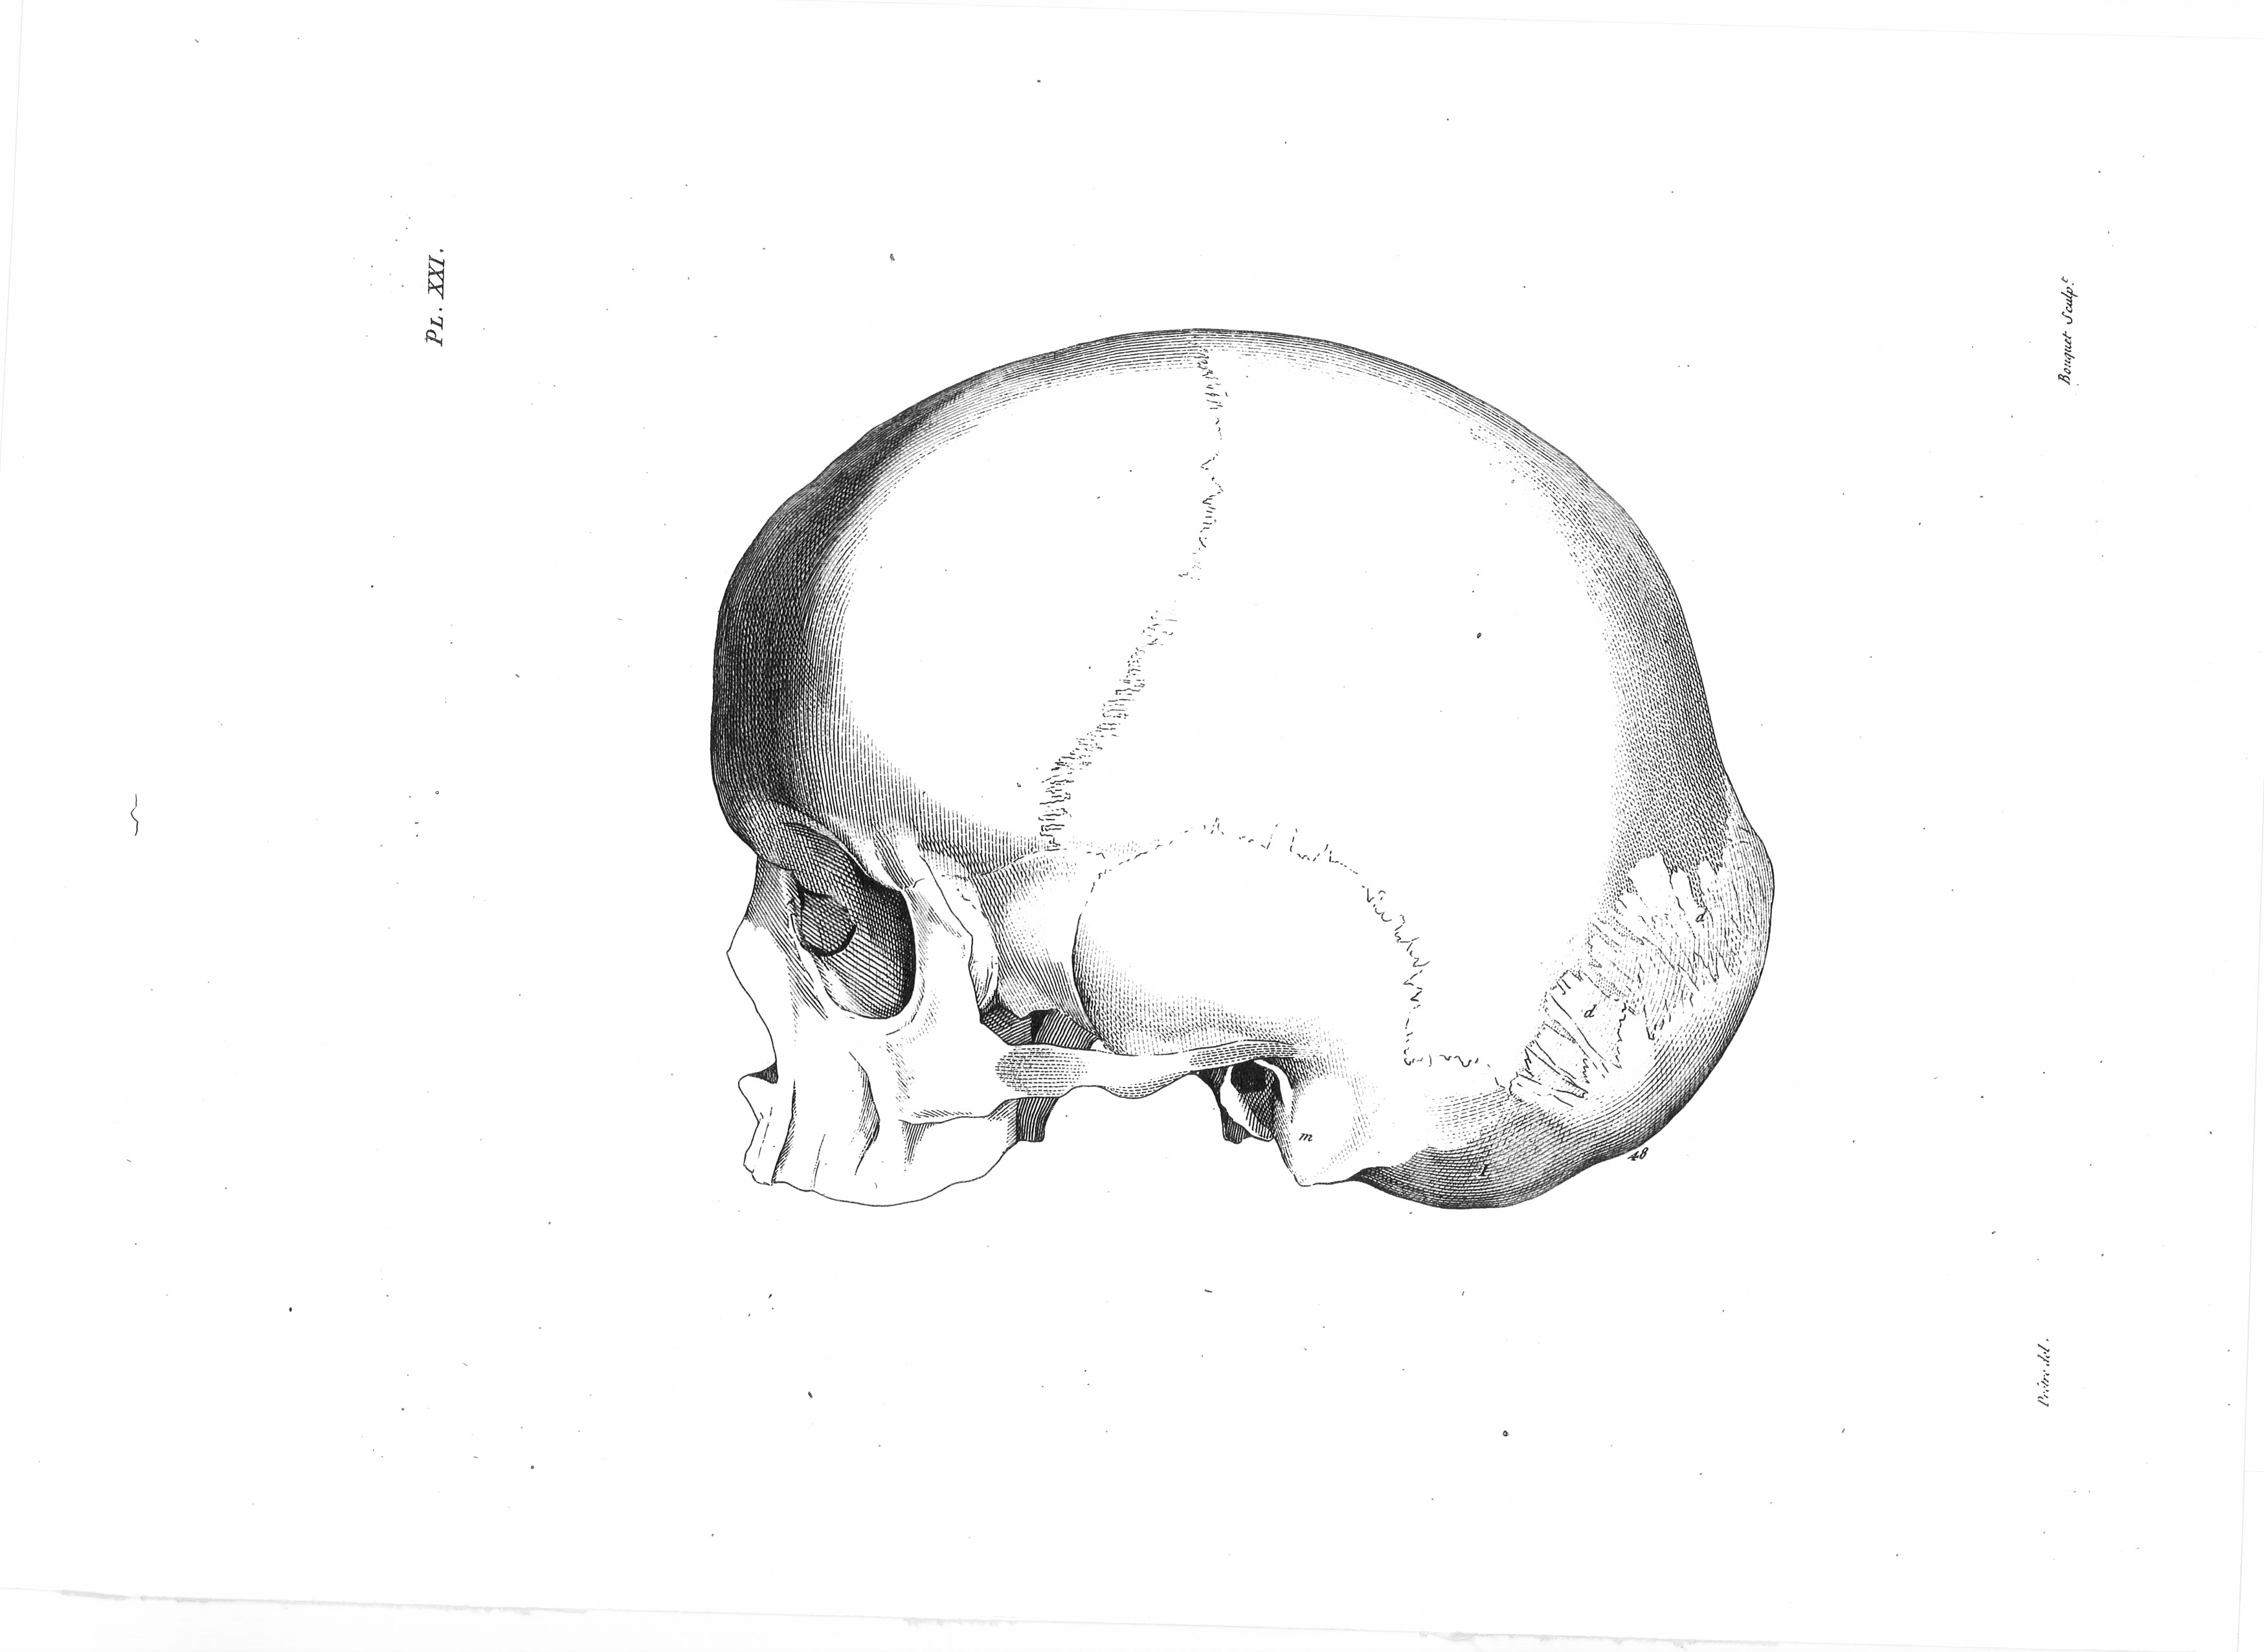

Gall, F. J. (1818). Anatomie et physiologie du système nerveux en général, et du cerveau en particulier, Avec des observations sur la possibilité de reconnoître plusieurs dispositions intellectuelles et morales de l´homme et des animaux, par la configuration de leurs têtes.

Librairie Grecque-Latine-Allemande, Vol. 3, I-XXXV u. 1-379 100 planches.